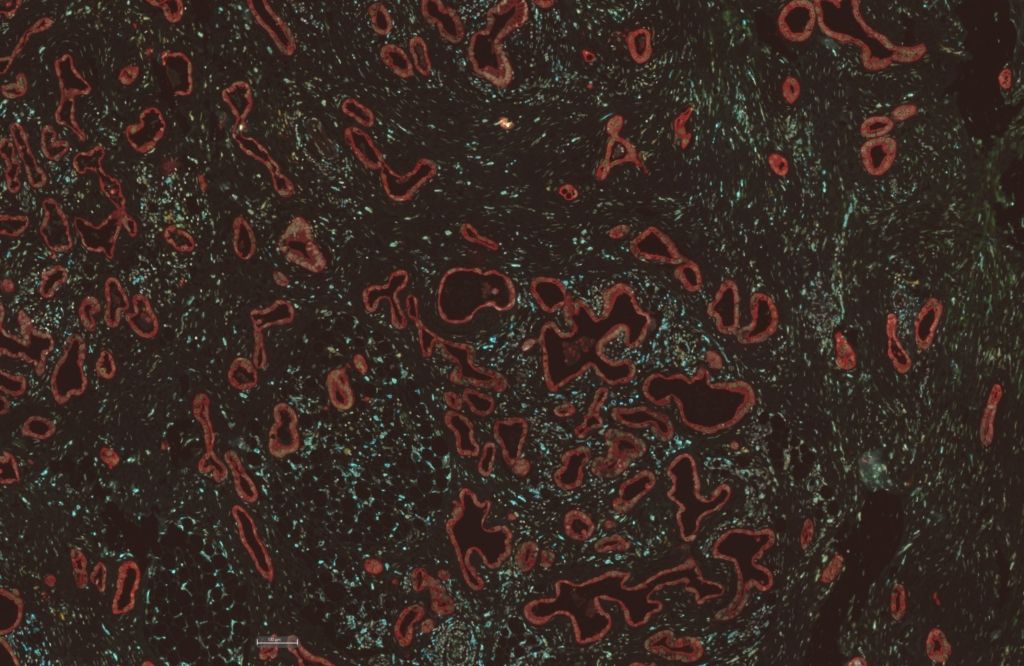

Ebenfalls von der Deutschen Allianz Pankreaskarzinom gefördert: Entschlüsselung und therapeutisches Targeting des PDAC-Ökosystems (DEFEAT-PDAC) unter der Leitung von Prof. Dr. Dieter Saur